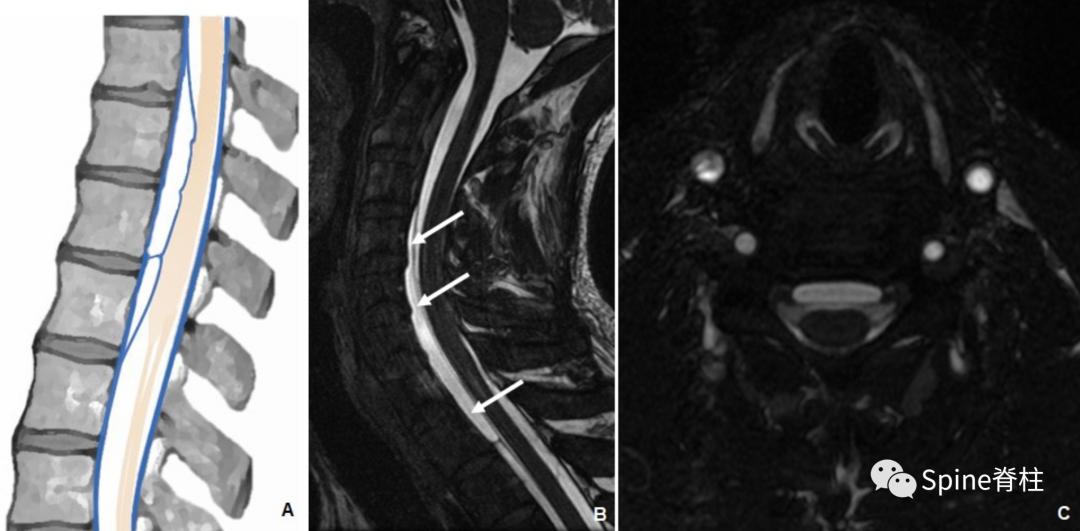

在MRI上,常发现与脊髓压迫相关的脑脊液等信号硬膜内囊肿,脊髓表面有广泛的扇形凹陷。CT或MR脊髓造影很重要,因为这些病变通常比蛛网膜下腔的其余部分充盈更慢(下图)。治疗主要以囊肿完全切除为主。

胸椎硬膜内蛛网膜囊肿的MR脊髓成像。矢状位T2加权像提示与脑脊液相同信号的硬膜内囊肿伴脊髓受压移位(箭头,图A)。矢状位注射钆对比剂后早期抑脂T1加权像显示病变的确切位置,并显示脊髓表面的扇形压迹(箭头,图B)。 模式图显示了硬膜内蛛网膜囊肿的典型外观(C)。横断位蛛网膜腔注射钆剂后早期(D)和延迟(E)抑脂T1加权像序列显示囊肿缓慢钆剂充填。